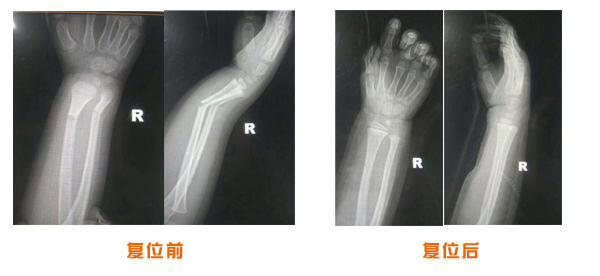

肥城市安駕莊梁氏骨科醫(yī)院是一所以梁氏手法正骨配合膏藥為特色的現(xiàn)代化專科醫(yī)院。

梁氏骨科術始創(chuàng)于清雍正年間,歷經(jīng)八代,至今已有三百年歷史。據(jù)1929年泰安縣志載“梁瑞圖先生,字增生,號蓮峰,安駕莊人,精岐黃并發(fā)明接骨,凡跌打車凡跌打車軋皮不破而碎骨者......【詳細】 |